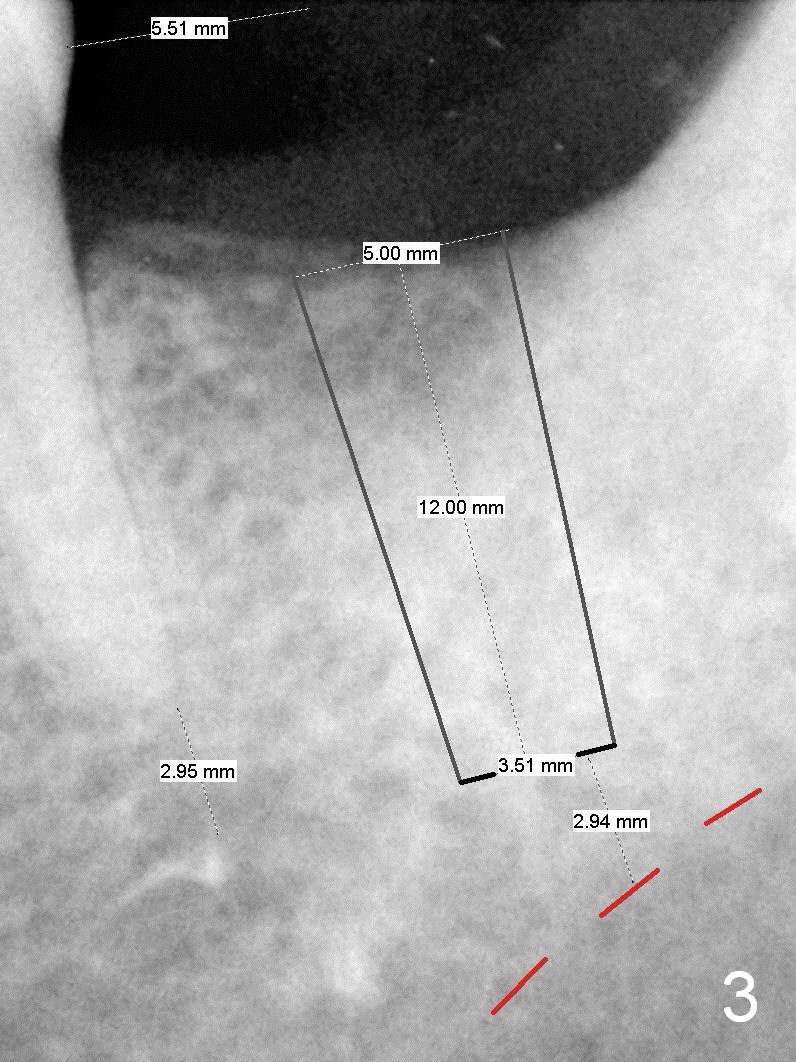

A 48-year-old lady is a dental phobic, requesting extraction of the lower left 2nd molar (Fig.1).   She returns for implant placement 9 months post extraction (Fig.2).  The ridge is mildly to moderately atrophic.  It appears that a 5x12 mm implant is appropriate for the site (Fig.3).  For safety, osteotomy is initiated at the depth of 10 mm; it appears that there is enough height for a 12 mm implant (Fig.4).  The depth is controlled by drill stopper (Fig.5 S).  Finally a 5x12 mm implant is apparently safely placed (Fig.6).  A healing abutment is placed and the incision is sutured with 4-0 Chromic gut (Fig.7).  Perio dressing is applied around the healing abutment for wound protection (Fig.8).  It appears that the healing abutment (Fig.8': *) helps stabilize the perio dressing, which remains in place 1 week postop.  When the perio dressing is removed, the wound around the healing abutment is healing (Fig.9).  There is no bone loss around the implant 3 months postop (Fig.10 (H: healing abutment), or 16 months postop (i.e., 9 months post cementation, Fig.11,12).  The patient complains of pain when she chews with the implant crown, but pain stops whenever she does not bite.  Percussion does not elicit any discomfort.  The gingiva is healthy.  There is possibility of the buccal plate being thin or the lingual plate being perforated in the submandibular fossa.  If the discomfort remains the same next 6 months, CBCT will be prescribed.